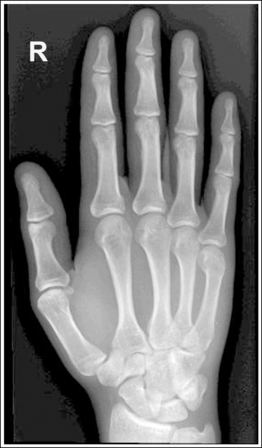

Hand: Posteroanterior Projection

The digits and metacarpals demonstrate a PA projection. The soft tissue outlines of the second through fifth phalanges are uniform, the distance between the metacarpal heads is equal, and the same midshaft concavity is demonstrated on both sides of the phalanges and metacarpals of the second through fifth digits.

• A PA projection of the hand is obtained when the patient fully extends the hand and rests the palmar surface flat against the IR (Figure 4-23).

• PA versus external oblique hand position. If the hand is not fully extended but is slightly flexed, it often relaxes into an external PA oblique projection when it is resting against the IR. A PA oblique hand projection is signified by slight superimposition of the third through fifth metacarpal heads and unequal soft tissue thickness and midshaft concavity on the sides of the phalanges. The metacarpals also show unequal midshaft concavity and spacing (see Image 20). Abducting the patient's arm and placing the forearm and humerus on the same horizontal plane, with the elbow flexed 90 degrees, assists in preventing an externally rotated PA oblique projection and will best demonstrate the wrist. This is important if a wrist condition is causing radiation hand pain. When the patient has been positioned in this manner, the ulnar styloid appears in profile on the image. Internal rotation of the hand is seldom a problem, because the thumb prevents this movement.

Image 20

No soft tissue overlap of adjacent digits is present.

The IP, MP, and CM joints are visible as open spaces, and the phalanges and metacarpals are not foreshortened. The thumb is demonstrated in a 45-degree PA oblique projection.

• When the hand and fingers are fully extended and a perpendicular central ray is centered to the third MP joint space, the IP, MP, and CM joints are demonstrated as open spaces and the phalanges and metacarpals are seen without foreshortening on the PA hand projection.

• Flexion of the hand causes poor alignment of the phalanges, metacarpals, and IP and CM joint spaces with the IR and central ray, resulting in closed joint spaces and foreshortening of the phalanges and metacarpals (see Image 21). The position of the first digit also changes when the image is taken with the hand flexed, because flexion rotates the first digit into a lateral projection.

Image 21

The third MP joint is at the center of the exposure field. The distal, middle, and proximal phalanges, the metacarpals, the carpals, and approximately 1 inch (2.5 cm) of the distal radius and ulna are included within the collimated field.

• Center a perpendicular central ray to the third MP joint to place it in the center of the collimated light field. This MP joint is situated just slightly distal to the head of the third metacarpal. Once the central ray is centered, open the longitudinal collimation to include the distal phalanx and 1 inch (2.5 cm) of the distal forearm. Transversely collimate to within 0.5 inch (1.25 cm) of the first and fifth finger's skin line.

• Either half of a 10- × 12-inch (24- × 30-cm) detailed screen-film IR placed crosswise or a single 8- × 10-inch (18- × 24-cm) digital IR placed lengthwise should be adequate to include all the required anatomic structures.

The hand was externally rotated, as indicated by the superimposition of the third and fourth metacarpal heads, the unequal midshaft concavity on either side of the phalanges and metacarpals, and the uneven spacing of the metacarpal heads. The tip of the second and third fingers has been collimated off, and less than 1 inch (2.5 cm) of the distal radius and ulna is included.

Internally rotate the hand until the palm and fingers are placed flat against the IR, and open the longitudinally collimated field to include the second and third fingertips and 1 inch (2.5 cm) of the distal radius and ulna.